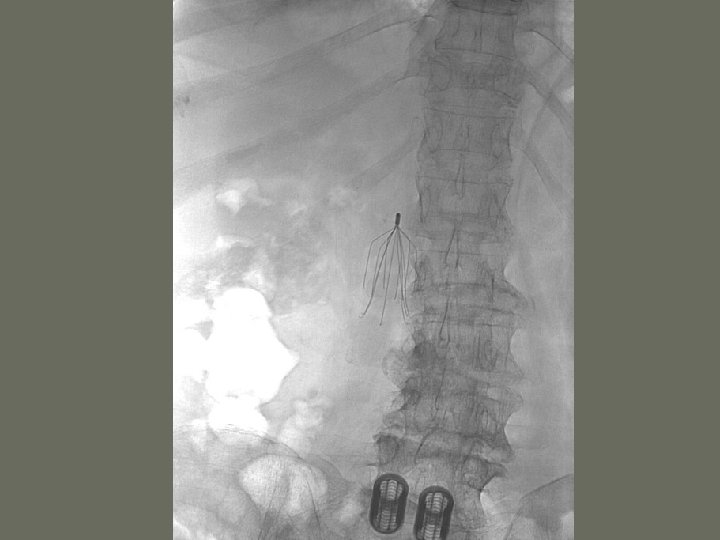

Interventional Procedures 7. Inferior vena cava filter • catches an _____ before is reaches the small vessels in the heart • prevents a pulmonary embolus